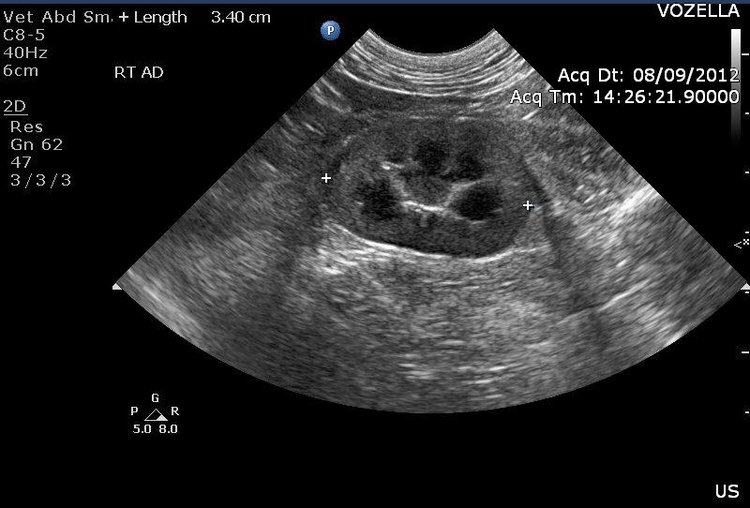

Kidney - Transverse View

It is common to visualize the kidneys during an ultrasound. Occasionally we can see stones or masses within the organ. It is also a landmark by which to locate the very small adrenal glands. Adrenal glands can secrete excess hormone causing hair loss, weight gain and urinary abnormalities- commonly referred to as Cushing's Disease.